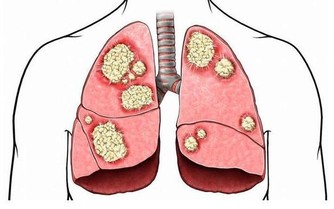

糖耐量異常就是指人體對葡萄糖的耐受能力出現了異常,人體分泌的胰島素對處理葡萄糖的能力,不如正常人迅速有效。這種異常通常能反應在血糖值上,即人體在進食2小時後,血糖超過正常的7.8mmol/L,但仍未達到11.1mmol/L,或者空腹血糖在6.2 mmol/L 至7 mmol/L 之間,這種叫做空腹葡萄糖受損。出現糖耐量異常的人處於正常人向糖尿病過渡的階段,雖然還沒有成為糖尿病患者,但卻極有可能發展為糖尿病,據統計,每年有5-8%的糖耐量異常患者發展為2型糖尿病。

一旦發展為糖尿病,則不可逆轉,所以這部分人要警惕,